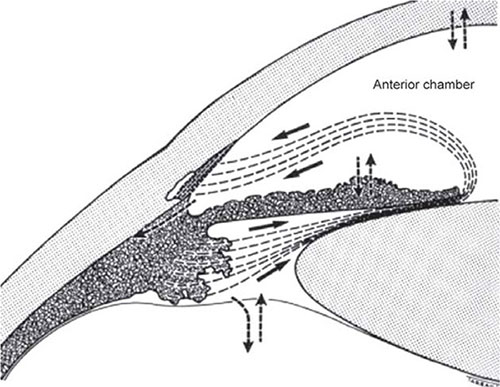

Uveoscleral Pathway

The anterior portion of the ciliary body extends into the anterior chamber angle and is inverted internally by the uveoscleral meshwork, behind the scleral spur. Since there is no continuous cellular layer on the anterior iris face aqueous humor has direct access from the anterior chamber into the ciliary body. From the ciliary body the aqueous drains into the supraciliary and suprachoroidal compartments, and from there either diffuses through the sclera, pass via scleral pores surrounding blood vessels and nerves, or gets absorbed into the uveal vascular system, including the vortex veins (the uveovortex outflow).27 This drainage pathway accounts for about 10 percent of the total bulk aqueous outflow in the human eye.

Drainage via the uveoscleral pathway is virtually independent of pressure at IOP levels greater than 7 to 10 mm Hg.28 The facility of uveoscleral outflow is approximately one twentieth the facility of trabecular outflow. The reason for the pressure independence of the uveoscleral pathway is not entirely clear, but might be the consequence of the complex nature of the pressure and resistance relationship between the various fluid compartments within the soft intraocular tissues along the route.29 8

FIGURE 1.7: Diagrammatic representation of the drainage pathways of the aqueous humor. The aqueous humor, formed in the posterior chamber (pc) by the ciliary processes, flows into the anterior chamber through the pupil. In normal eyes, the main drainage route for bulk outflow is the conventional drainage pathway constituted by the trabecular meshwork and Schlemm's canal (SC). Subsidiary drainage routes include (1) the uveoscleral and uveovortex, that is, through the anterior face of the ciliary body into the suprachoroidal space; (2) exchange across the anterior vitreous face; (3) exchange across the iris vessels; and (4) exchange across the corneal endothelium. The role of 2,3 and 4 in the net removal of aqueous humor appears to be insignificant because the net loss is equivalent to net gain through a two-way exchange.(From Tripathi RC and Tripathi BJ in Duane TA and Jaeger EW (eds)(1982) Biomedical Foundations of Ophthalmology, Vol. 1, published by Harper and Row)

Under normal circumstances there is always a positive pressure-gradient between the suprachoroidal and intraorbital spaces, with the result that fluid and solutes can easily exit the eye. At low IOP levels, the net pressure gradient across the uveoscleral pathways is apparently so low that uveoscleral drainage decreases.30 The absence of an outflow gradient from the suprachoroid may contribute to the development of choroidal detachments seen during the ocular hypotony that sometimes follow intraocular surgery.31

Uveovortex Pathway